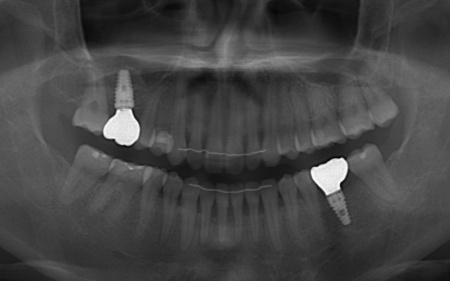

| カウンセリング | 拝見したところ、右上と左下の奥歯に強い痛みが出ていました。 レントゲンで確認した結果、どちらも歯の根が割れていることが判明しました。 歯の根が割れたまま放置すると噛むときの痛みが続くだけでなく、炎症が広がって周囲の歯や骨にまで影響を及ぼすおそれがあります。 また、上下の歯を噛み合わせた際に前歯が噛み合わず隙間ができる開咬(かいこう)と呼ばれる噛み合わせも見られました。 以上のことから、抜歯後に歯を補う治療と噛み合わせを改善するための治療が必要と診断しました。 |

患者様は「健康な歯をできるだけ守りたい」との理由から、③のインプラント治療を希望されました。 まず、右上と左下の奥歯を抜歯しました。 矯正がある程度進んだ段階で、右上と左下のインプラント手術を実施しました。 インプラント手術後は矯正治療の仕上げを行い、装置を外しています。 治療終了後、下前歯の間に見られる三角形のすき間(ブラックトライアングル)が気になるとのご相談がありました。 |

| 費用 | 約2,100,000円 【内訳】 矯正治療、ソケットリフト、GBR、インプラント2本 |